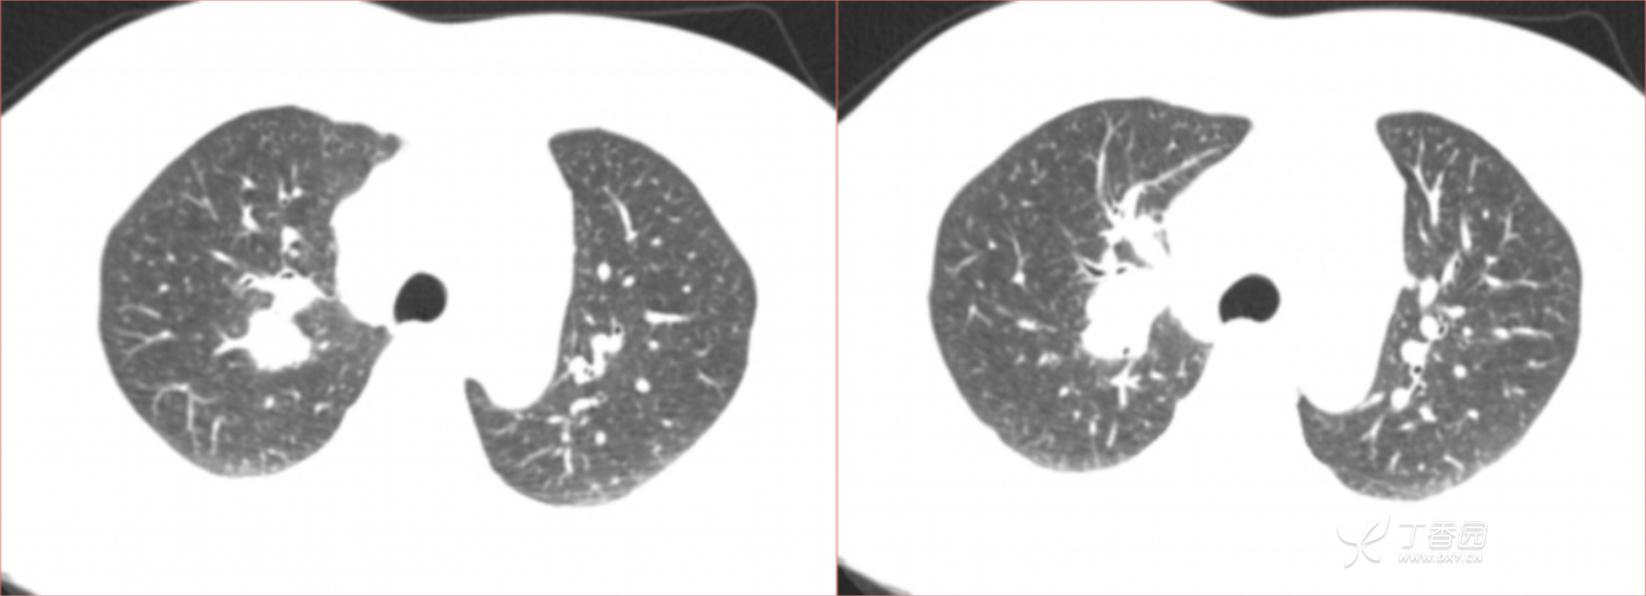

1月特别精彩病例|阵发性刺激性咳嗽,咳少量白色粘液痰1周,期待你的挑战【结果公布】

患者年龄:34岁

简要病史:患者一周前无明显诱因出现阵发性刺激性咳嗽,咳少量白色粘液痰,咳嗽无明显昼夜节律性,无发热、畏冷、寒战,无头痛、胸闷、胸痛,自行服药后 (具体不详) 症状无缓解,3天前当地医院胸片检查示右上病变

辅助检查:肺肿瘤标志物: 神经元特异性烯醇化酶(NSE): 35.72ng/ml(参考值0-16.3);非小细胞肺癌相关抗原211、癌胚抗原、糖类抗原125、铁蛋白、鳞状细胞癌抗原未见异常